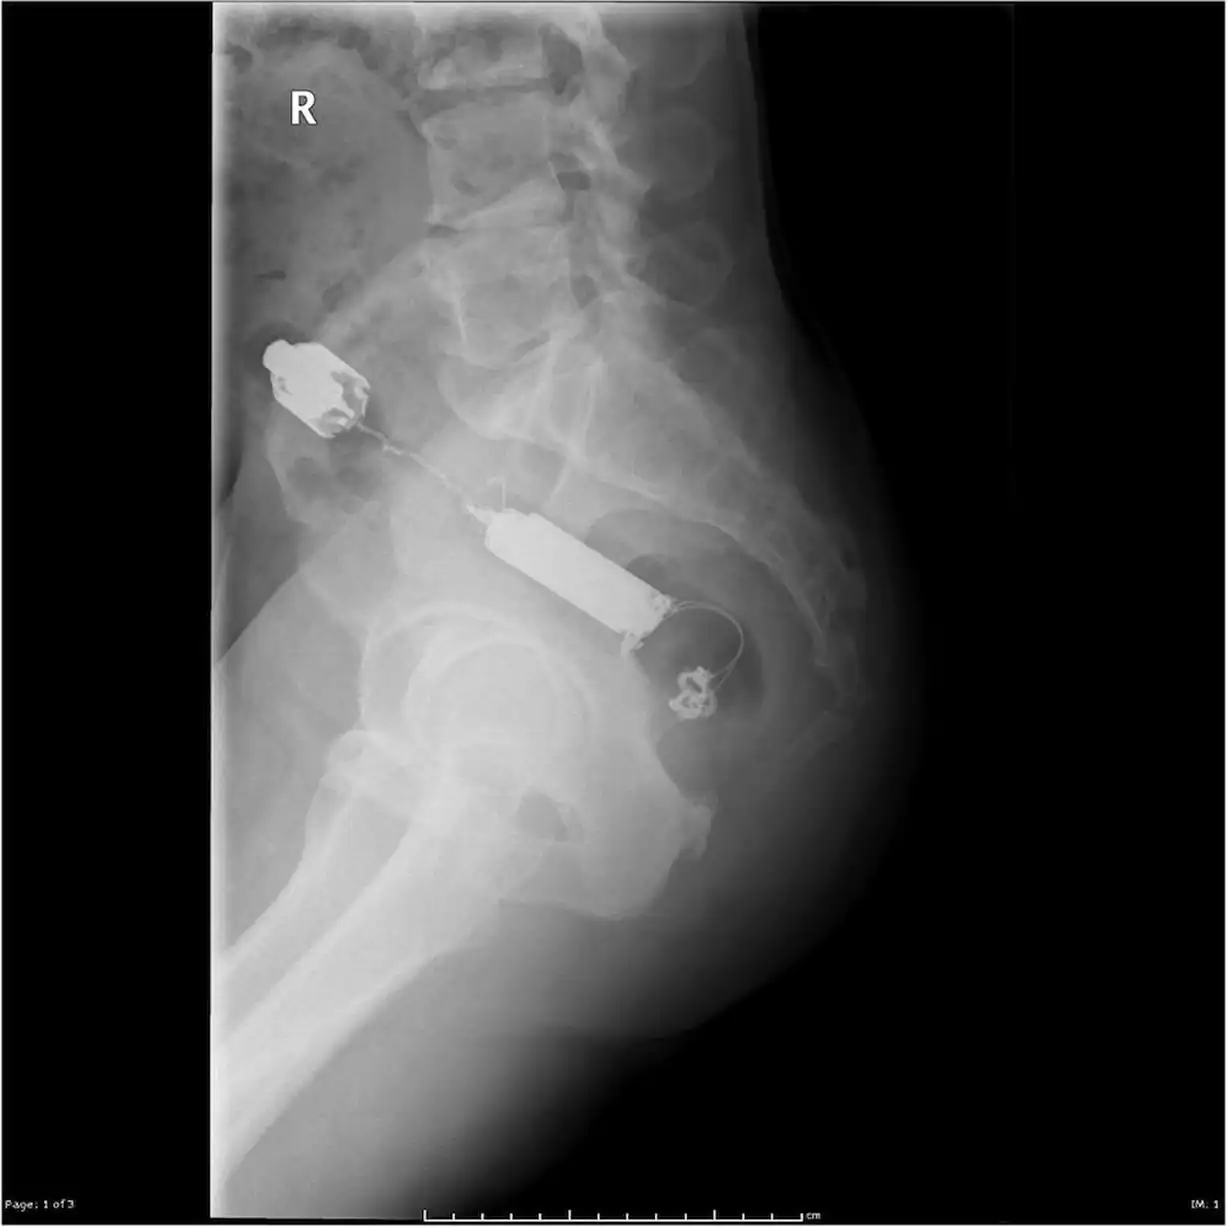

Врачебные находки в интимных местах

Или как впихнуть невпихуемое :lol: